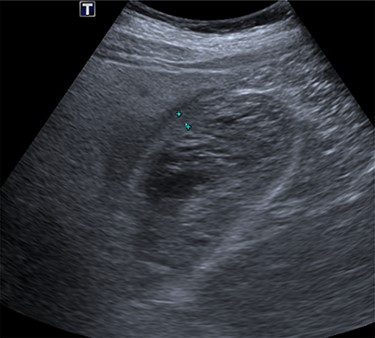

Intravenous broad-spectrum antibiotics were commenced, and the patient was admitted to the surgical ward and fasted for an MRI liver with gadolinium contrast. The MRI revealed no convincing features of malignancy; however, the gallbladder was distended with heterogeneous, predominantly low T1 and T2 content and demonstrating no internal enhancement, as seen in Fig. 2. These findings suggested the presence of sludge and/or luminal blood clod, and a further ultrasound (US) of the gallbladder was recommended. US scan, as shown in Fig. 3, confirmed cholecystitis with no evidence of cholelithiasis.

MRI scan of the patient, showing a distended gallbladder with low T1 and T2 content demonstrating no internal enhancement.